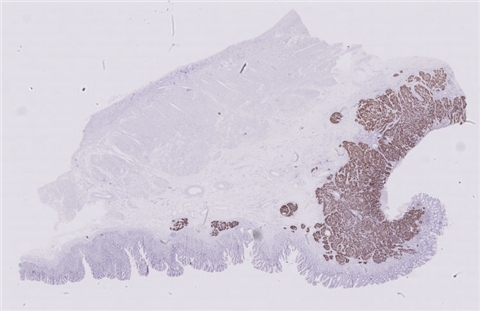

患者详情: 发现肛门肿物8月余,大便带血次数增多。外院病理检查:腺癌伴类癌分化。

大体所见: 肠管一段,直径3cm,长22cm,紧邻肛侧切缘、距另一侧切缘19cm处可见一菜花样肿物,大小6*6*5cm,切面灰白灰红色,质脆,侵及肠管全层,共取11块。

免疫组化: 蜡块一:CD20(-)、PAX-5(-)、CD3(-)、CD43(-)、EMA(局灶弱+)、CKL(-)、CK8/18(+)、CgA(-)、syn(+)、CD56(+) 蜡块二:GST-π(+/-)、TOPOII(+)、PGp(3+)、EGFR(-)、VEGF(+/-)、P53(小于3%+)、CERbB-2(-)

医院: 九江学院附属医院